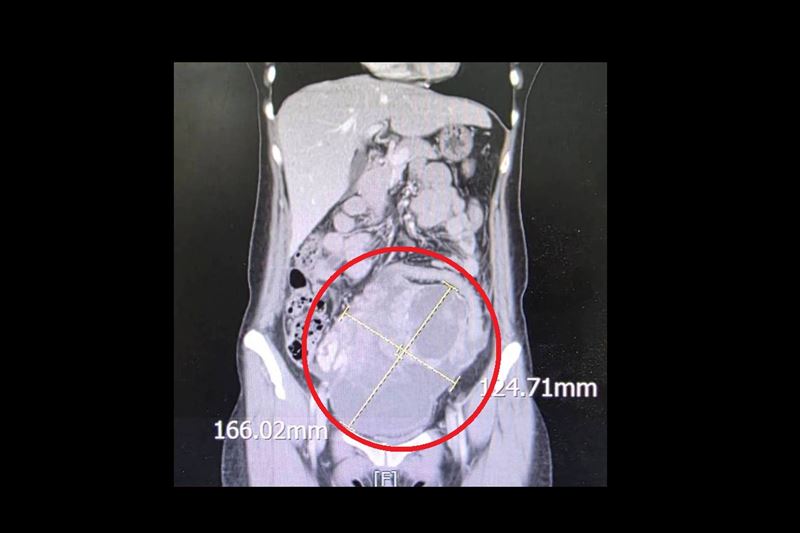

一名44歲未婚女性,持續兩週感到腹痛、腹脹且食慾不振,原以為是腸胃不適,就醫檢查後竟在腹部發現直徑高達 16公分的巨大腫瘤,且癌症指數(CA-125)飆升至 900 U/ml(正常值為 <35 U/ml)。大千綜合醫院婦產科劉榮啟醫師緊急安排手術切除子宮及兩側卵巢,術後病理報告證實為罕見的「同步性子宮內膜癌與卵巢癌(SEOC)」。在醫療團隊治療下,病人至今已成功抗癌滿5年,復原狀況良好。

該名病人的診斷結果均屬早期(分別為 1c 期與 1a 期)。在接受完整的手術切除後,為了確保徹底清除癌細胞,病人配合進行了6次化學治療,並接受了第2次腹腔鏡探查手術追蹤。至今五年過去,病人定期回診檢查各項指標均正常,已正式跨越癌症醫學上重要的「五年存活期」門檻。